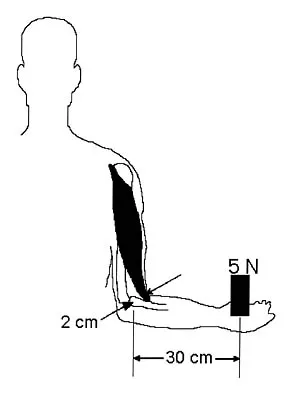

A 39-year-old woman fell onto her flexed elbow and sustained a comminuted displaced radial head and neck fracture. Radiographs confirm concentric reduction of the ulnohumeral joint. Examination reveals pain with compression of the radius and ulna at the wrist. What is the best treatment for the radial head fracture?